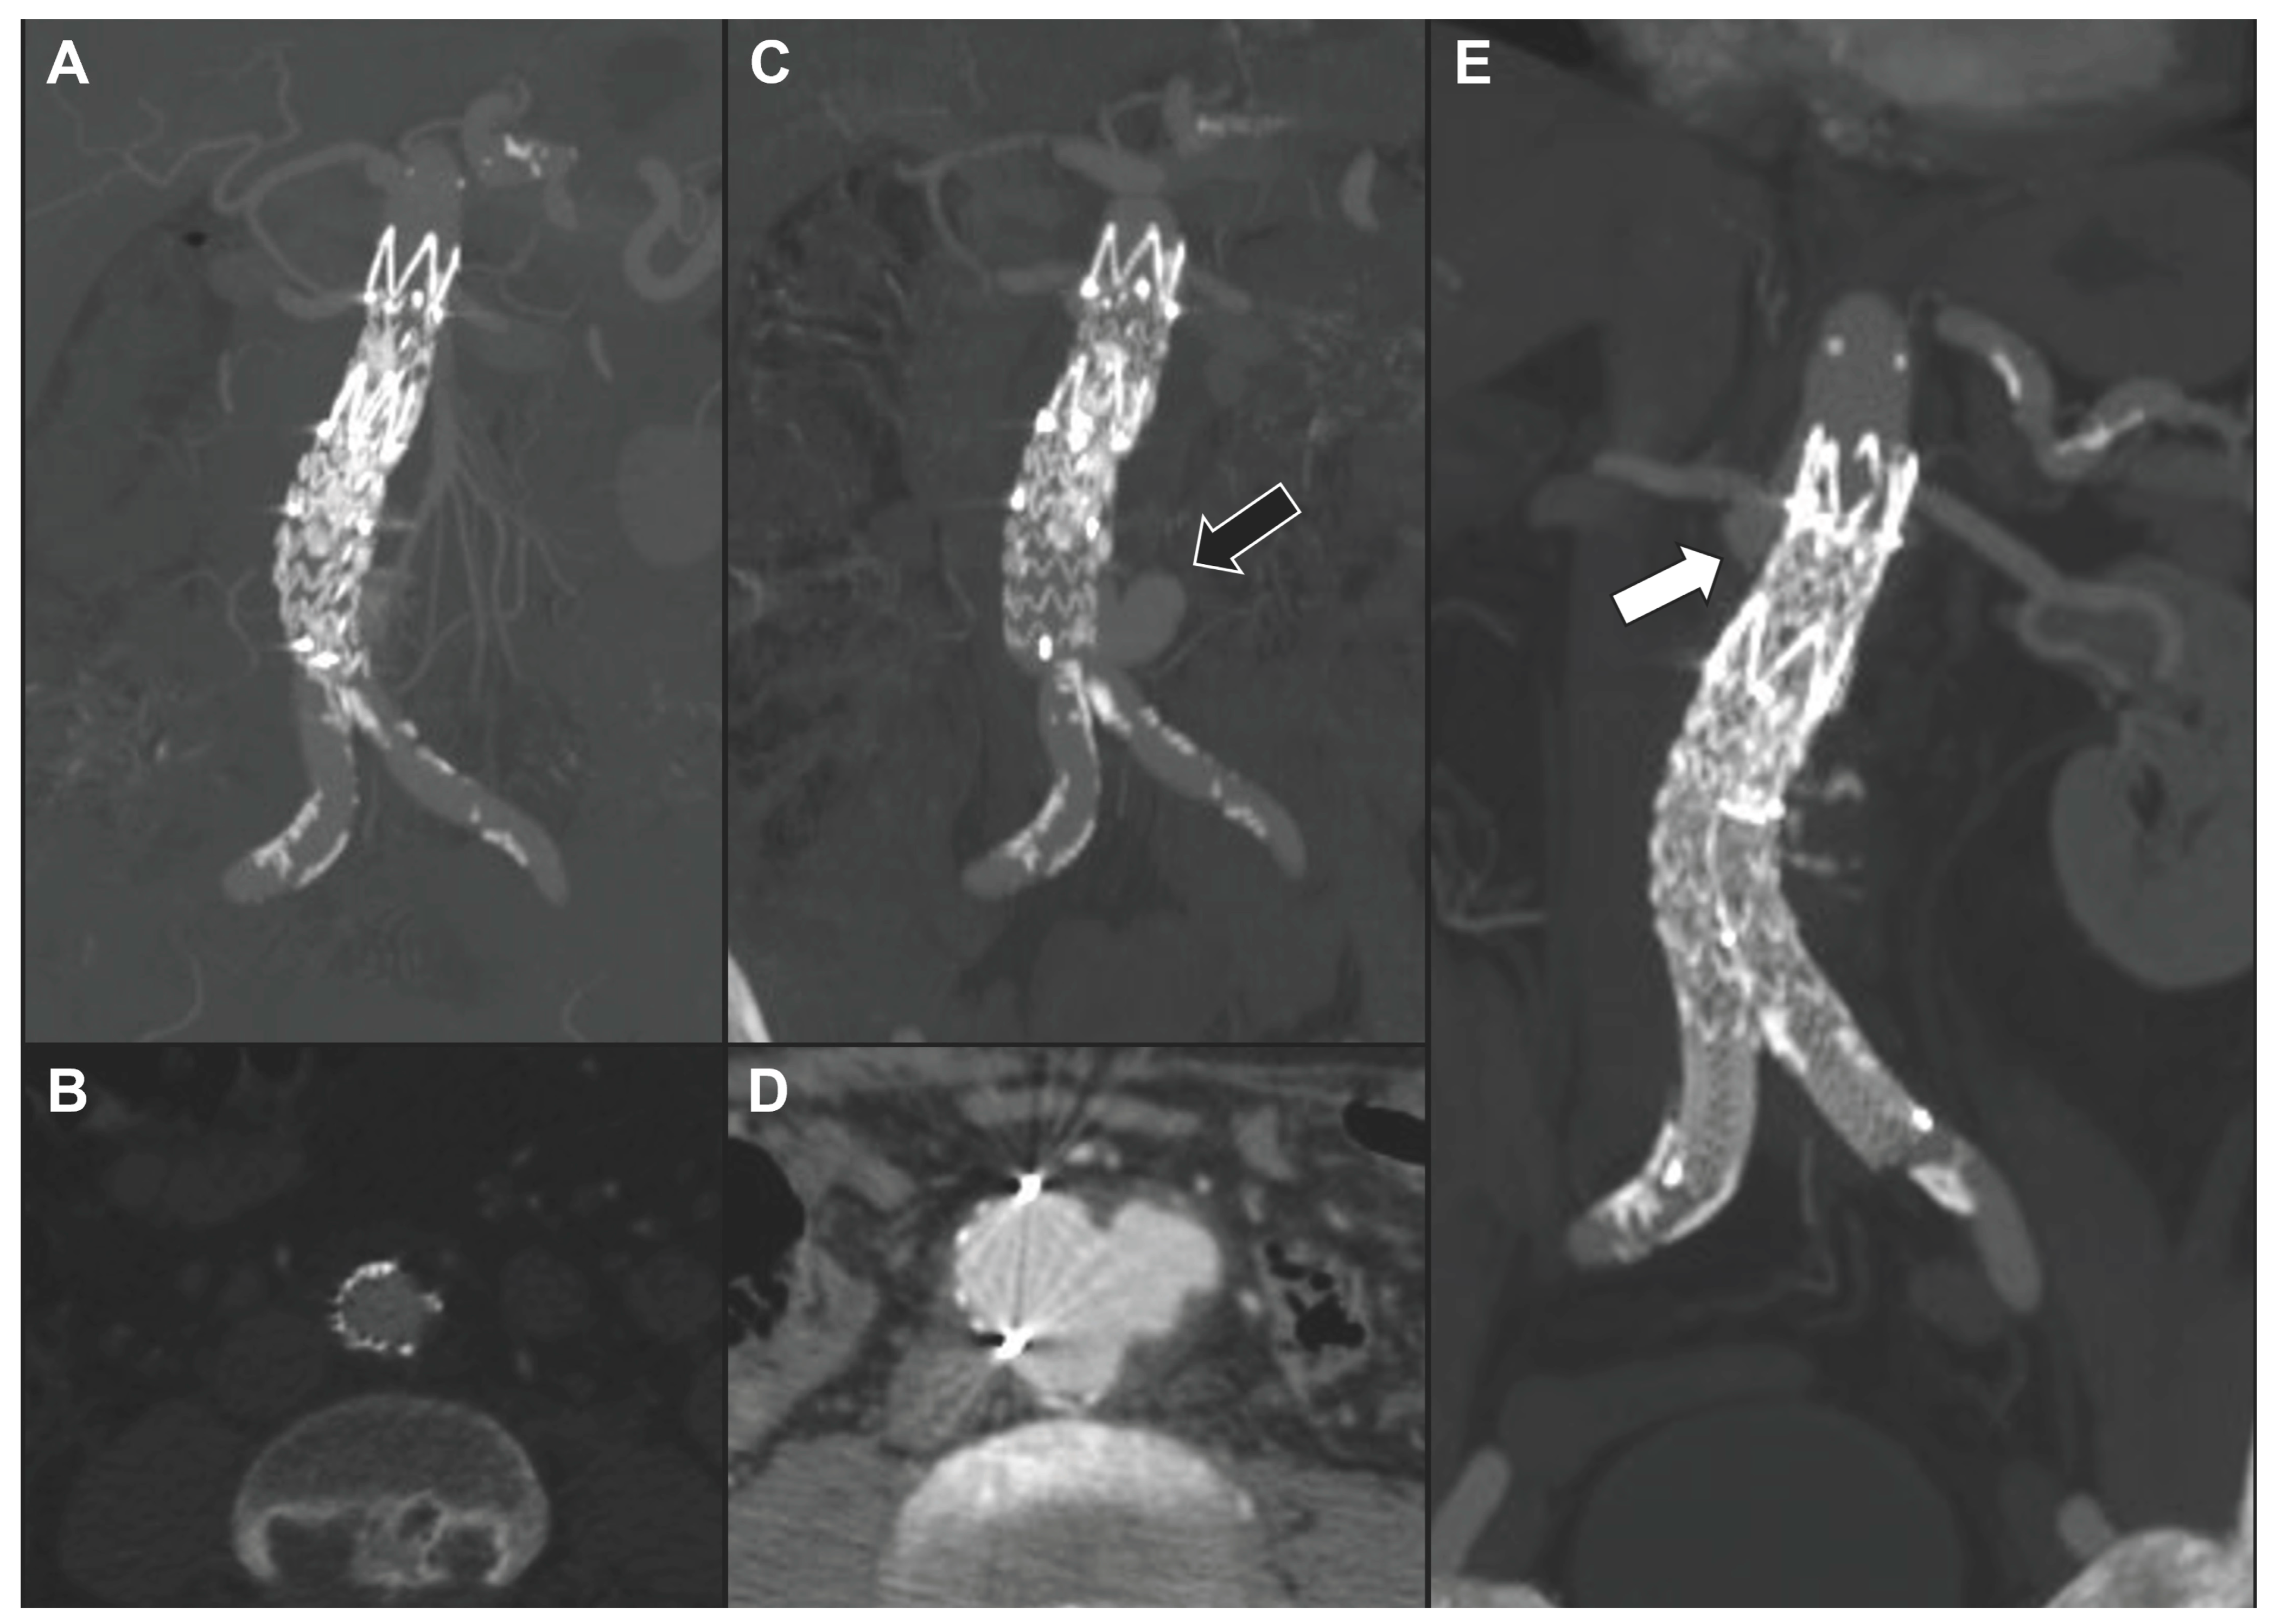

| 2 | M | 70 | Spondylodiscitis | Staphylococcus aureus | No | Contained ruptured type I TAAA | Linezolid | TEVAR ± SMA Chimney ± RRA Periscope ± CT embolization | Alive | 52 | Stability with type II endoleak | - |

| 7 | M | 78 | Spondylodiscitis | Staphylococcus aureus | No | Symptomatic multi-lobular type IV TAAA | Oxacyllin | BEVAR | Alive | 36 | Stability | - |

| 8 | M | 72 | Sepsis in pre-existing TAAA | Escherichia coli | Yes | Symptomatic saccular type IV TAAA ± peri-aortic gas | Amoxicillin ± Clavulanate | BEVAR | Alive | 11 | Stability ± non-contiguous new arch lesion | TEVAR |